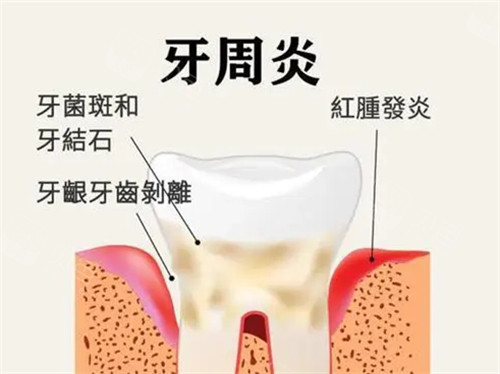

牙齿松动是许多人面临的口腔难题,而牙周炎正是其背后的主要诱因之一。当牙龈红肿、出血等症状未被及时干预,炎症可能持续破坏牙周组织,导致牙齿失去支撑出现松动。面对这种情况,单纯依靠药物或偏方往往难以解决问题,需通过科学的治疗方案改善牙周健康。本文将结合临床实践,详细解析牙周炎合并牙齿松动的综合治疗策略。

牙周炎的治疗需遵循“先控炎,后修复”的原则。对于已出现牙齿松动的患者,首要任务是通过规范化的牙周治疗消除致病因素,为后续修复创造条件。

超声洁治与龈下刮治:利用超声波震荡清除牙龈上方的牙石,通过手工器械深入牙周袋内刮除根面感染物质及病变牙骨质。这项操作能有效减少口腔内细菌负荷,为牙龈愈合提供清洁环境。

药物治疗辅助:局部使用氯己定漱口水或米诺环素软膏,可抑制牙周袋内致病菌繁殖。对于急性发作期患者,医生可能建议短期口服抗生素控制感染。